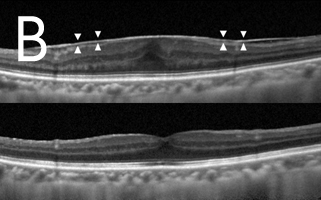

近視超過600度的人士眼球拉長的情況非常嚴重,黃斑點亦被拉扯變薄。再加上不正常的玻璃體和黃斑點視網膜前膜增生之牽引,導致黃斑點神經組織裂開,甚至喪失視力。如未能及早施行適當治療,黃斑點裂損有可能進一步惡化,導致黃斑點穿孔和黃斑點視網膜脫落。利用光相干性斷層造影可及早發現並作出準確的診斷(圖3)。治療方法是施行扁平部玻璃狀體切除術,移除凹前表質玻璃體,並進行氣體和液體交換,治療可治癒大部份病人的黃斑點凹位,而大部份病人在手術後亦無須保持俯臥。

![]() ![]() Photo 3: 圖3:光相干性斷層造影(OCT):(A)發現大量黃斑點裂損,並有視網膜黃斑點凹位脫落跡象,且在黃斑點凹位附近發現不正常的玻璃體牽引(箭頭所指位置)。(B)手術後六個月黃斑點裂損的情況大有改善,減少視網膜黃斑點脫落的幅度。 |